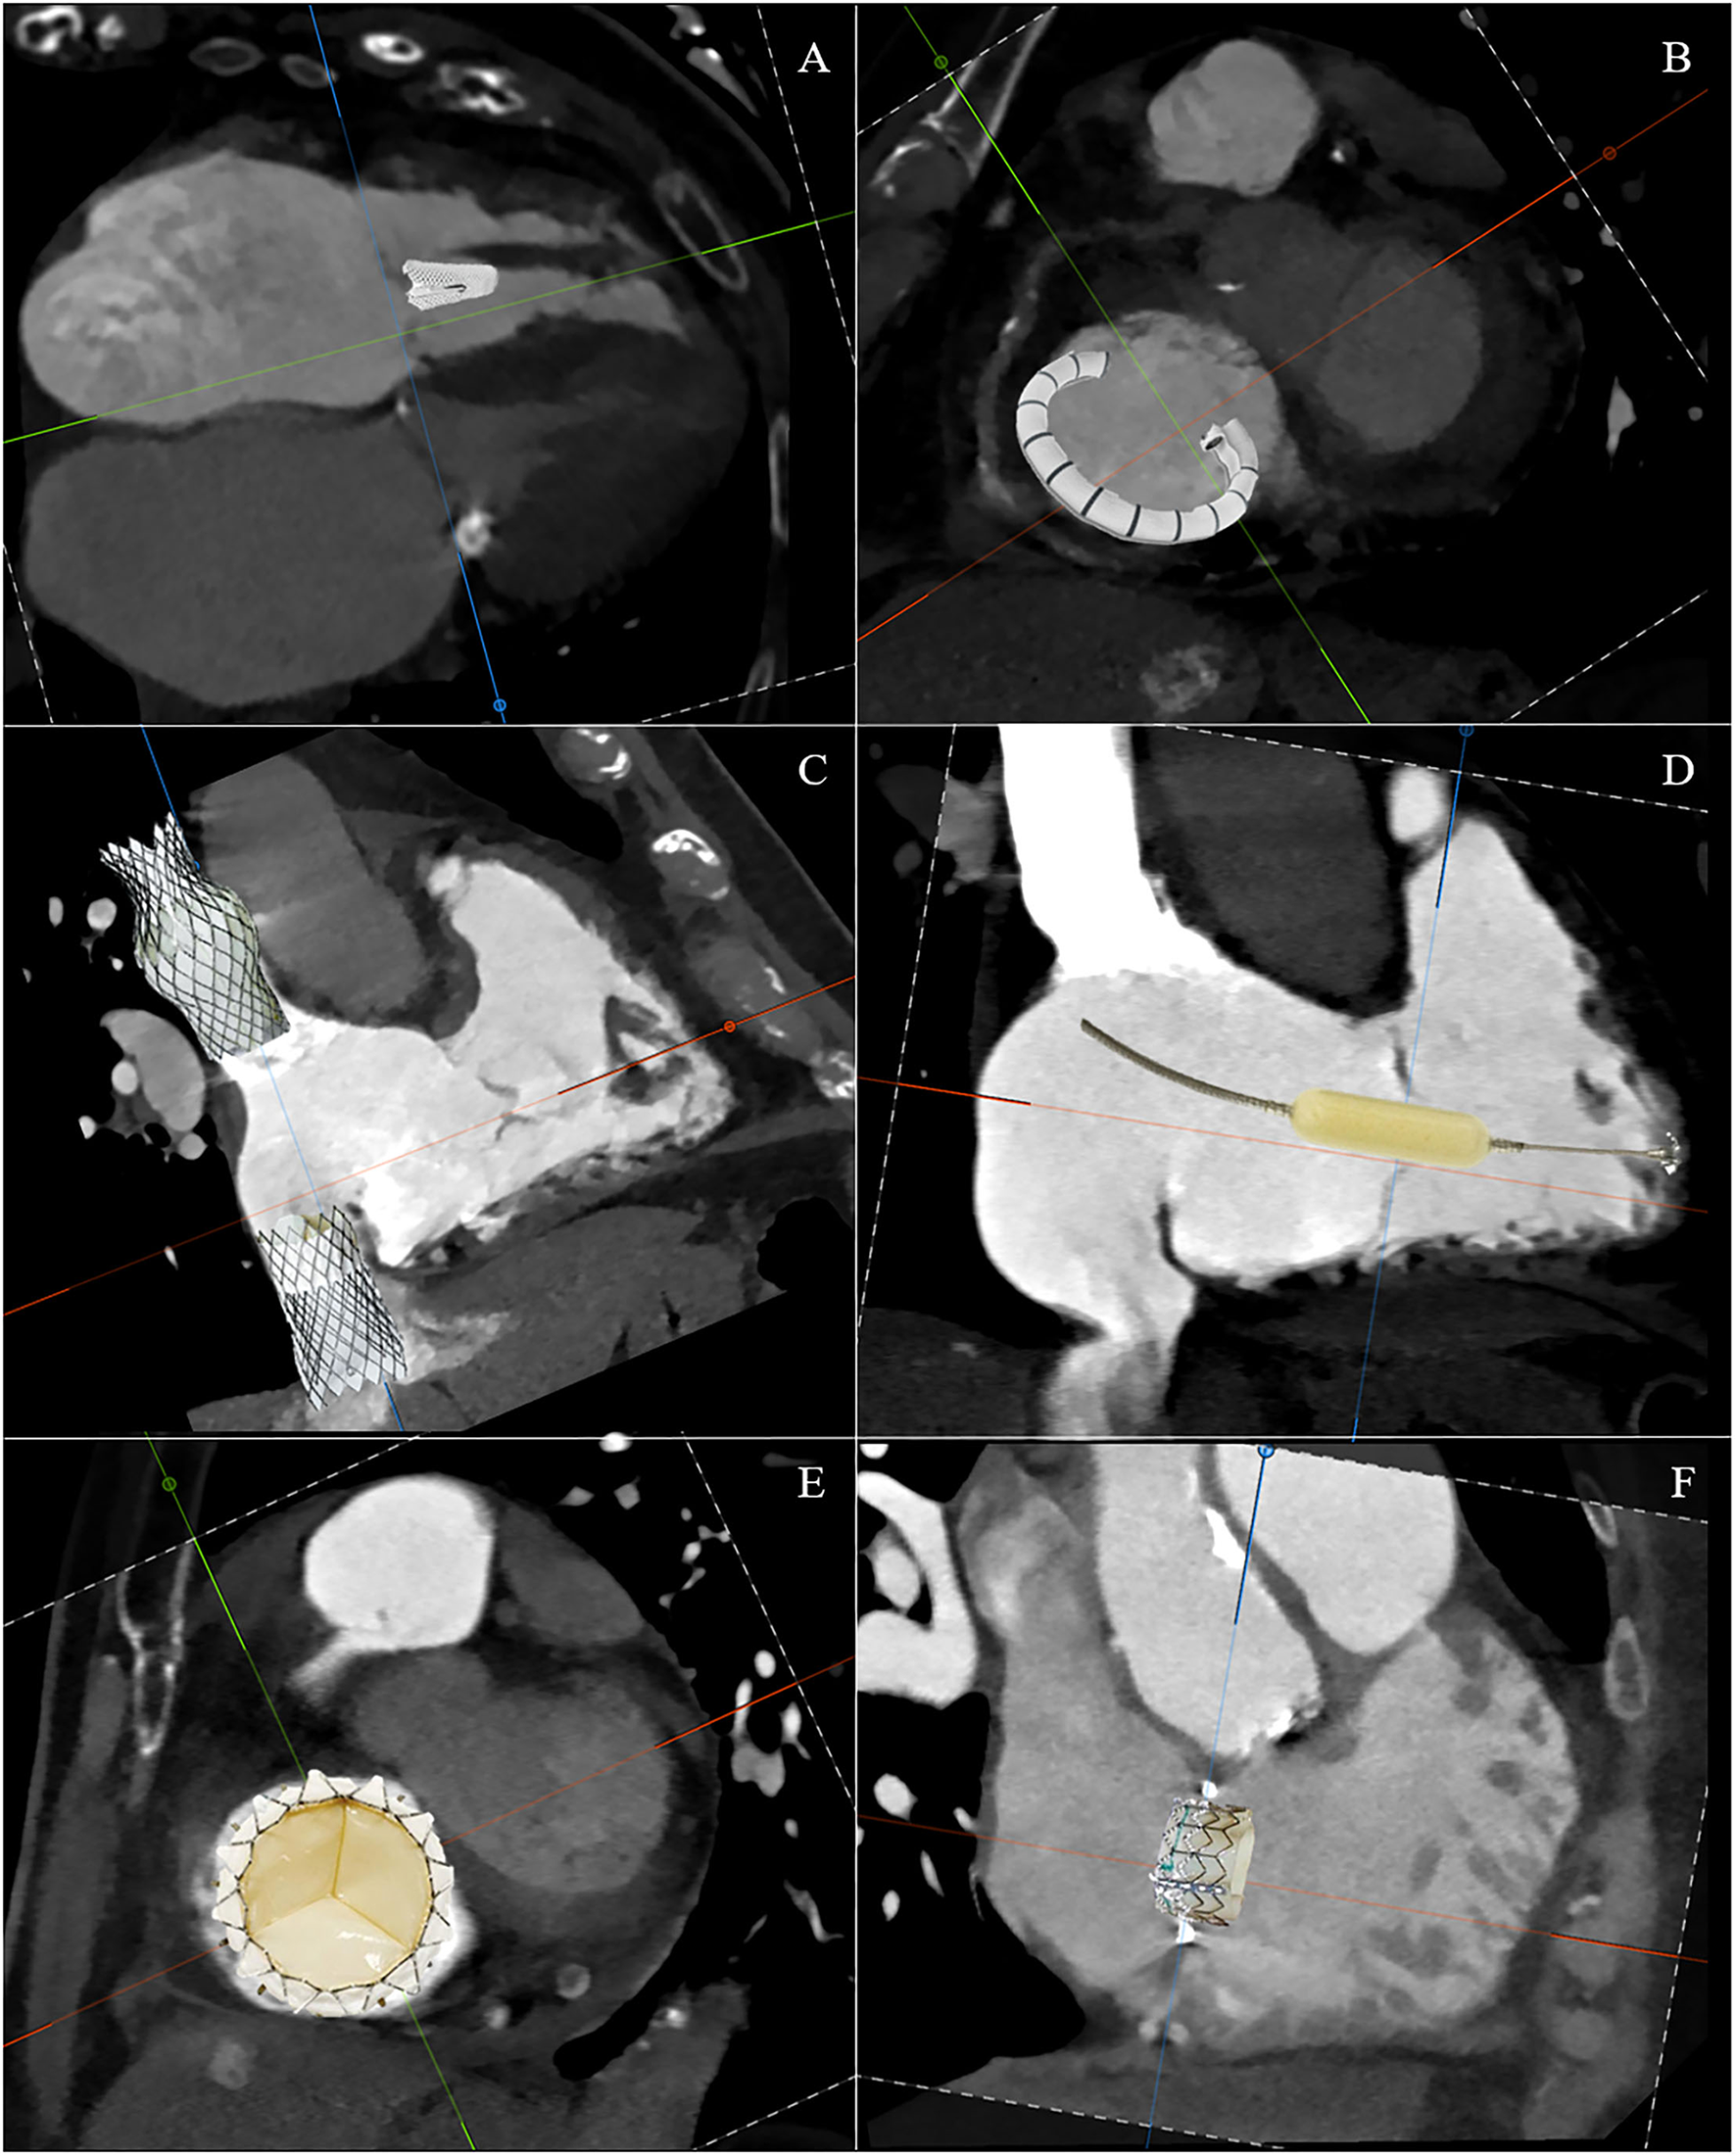

Furthermore, assessment of the RCA course and its distance to the annulus, simulation of virtual device implantation, and prediction of an optimal projection angle are part of a comprehensive CT-based pre-procedural assessment (Figure 6) (34).

The TTVI can be divided into these five domains: edge-to-edge repair, tricuspid annuloplasty, caval implants, spacer, and total valve replacement (Figure 7). However, there are a number of issues that require a thorough understanding of the morphology of the right side and the process by which secondary TR occurs in order to recognize the role of transcatheter interventions. First, there are multiple access sites possible: vena cavae, direct transatrial, and direct transapical. Second, there are multiple targets of device attaching: annulus, leaflets, vena cavae, and myocardium. Third, the presence of adjacent structures, which on the one hand can be anatomical markers during the procedure, but on the other hand must also be taken into account to avoid complications. Finally, understanding the anatomy and pathophysiology of the disease in an individual patient is the critical point for selecting a specific device for that patient. Table 1 summarizes the anatomic findings and the relative considerations for TTVI.

Figure 7

Schematic CT reconstruction of available techniques for transcatheter tricuspid valve interventions: edge-to-edge repair (A), tricuspid annuloplasty (B), caval implants (C), spacer (D), total valve replacement (E), and valve-in-ring replacement (F).